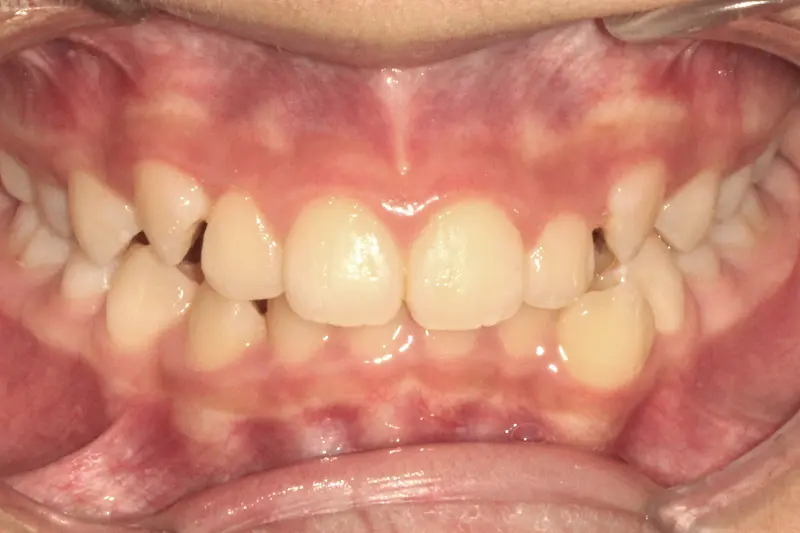

The Diagnosis

Anterior Open Bite with Class III tendency (Underbite). The front teeth did not touch, making chewing difficult and placing excessive force on the back teeth.

The Engineering

Using Invisalign with "SmartForce" attachments, we intruded the posterior teeth (molars) to close the bite at the front. We simultaneously corrected the underbite relationship using precision-cut elastics, achieving full function without surgery.